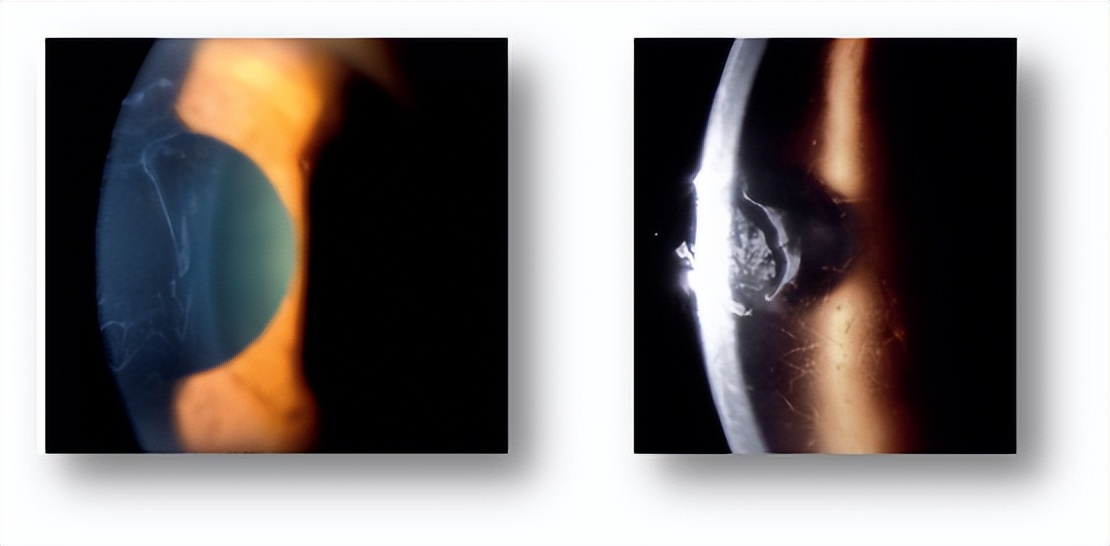

1.角膜上皮基底膜营养不良(又称为地图-点状-指纹状营养不良),即是由于角膜上皮基底膜发育异常,导致反复上皮缺失;

2.角膜格子样营养不良,其临床特征为实质浅层与Bowman层内的不规则分支状白色细条和混浊点,逐渐扩展增粗增大,交织成网格状;同样可伴有复发性上皮缺损。

图1. 原发性角膜上皮病变,左图为角膜上皮基底膜营养不良,右图为角膜格子样营养不良